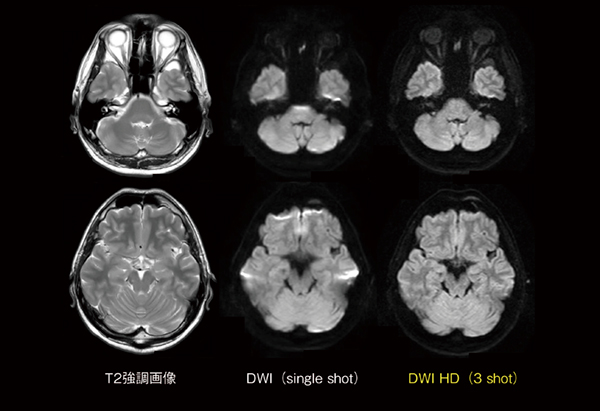

画像歪みの少ない拡散強調画像

今回,磁化率による画像歪み(磁化率アーチファクト)の少ない拡散強調画像としてDWI HD(HD:High Definition)が搭載されました(図9)。EPI(echo planner imaging)シーケンスを主体とする拡散強調画像は,EPI特有の磁化率による画像歪みが生じやすいことで知られています。これは,1回の励起でk空間を充填するシングルショット撮像に起因するものであり,画像歪みを低減するためにパラレルイメージングなどを用いて位相数を少なくするような手法が一般的に用いられています。DWI HDは,EPIシーケンスにおいて,画像情報を分割して取得するマルチショット撮像における被検者の生理的な体動の影響により各ショットの信号間に発生する位相のズレを補正し,かつ,画像歪みを低減した画像を得ることができます。DWI HDはシングルショット撮像よりも磁化率による歪みが少なく,高い空間分解能で撮像できるので,内耳・前頭洞付近の画像歪み低減が期待できます。

図9 DWI HDによる画像歪みの低減効果

DWI(single shot)では内耳や前頭洞付近に画像歪み(磁化率アーチアクト)が発生しているが,DWI HD(3 shot)では,画像ボケも軽減し,なおかつ画像歪みも低減していることがわかる。